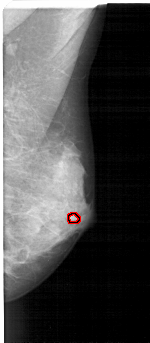

A_1606_1.RIGHT_MLO

RIGHT_MLO LINES 5131 PIXELS_PER_LINE 2236 BITS_PER_PIXEL 12 RESOLUTION 43.5 OVERLAY

FILE: A_1606_1.RIGHT_MLO.OVERLAY

TOTAL_ABNORMALITIES 1

ABNORMALITY 1

LESION_TYPE MASS SHAPE LOBULATED MARGINS OBSCURED

ASSESSMENT 4

SUBTLETY 2

PATHOLOGY BENIGN

TOTAL_OUTLINES 1

BOUNDARY